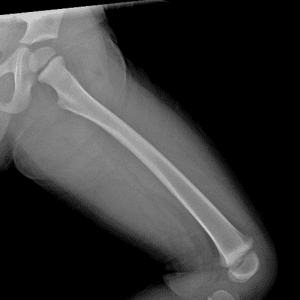

Pediatric Radiographs